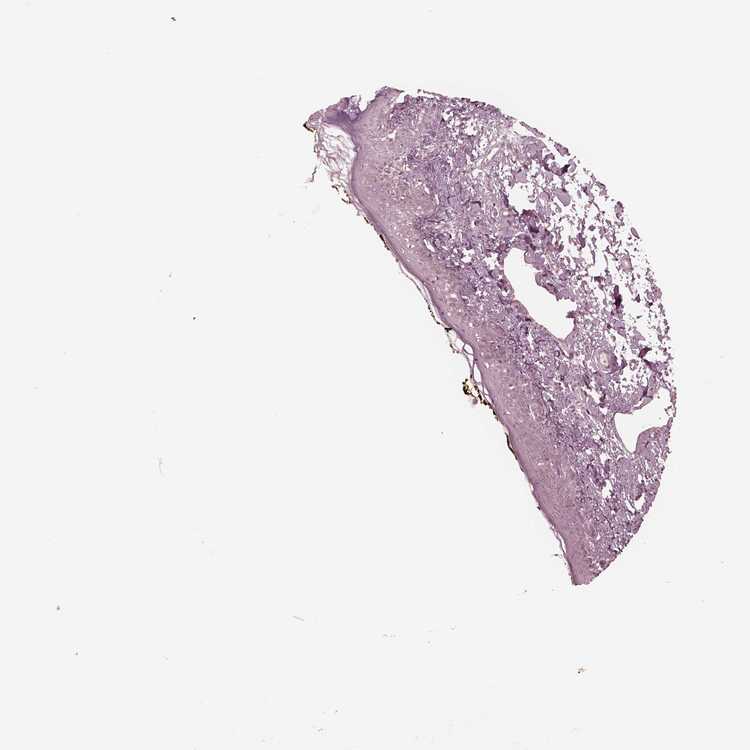

SKIN 1 - Antibody stainingi

Antibody staining in the annotated cell types in the current human tissue is reported as not detected, low, medium, or high, based on conventional immunohistochemistry profiling in selected tissues. This score is based on the combination of the staining intensity and fraction of stained cells.

Each image is clickable and will lead to virtual microscopy that enables deeper exploration of all samples and also displays staining intensity scores, fraction scores and subcellular localization as well as patient and tissue information for each sample.

Antibody HPA038811

Langerhans Not detected

Fibroblasts Not detected

Keratinocytes Not detected

Melanocytes Not detected